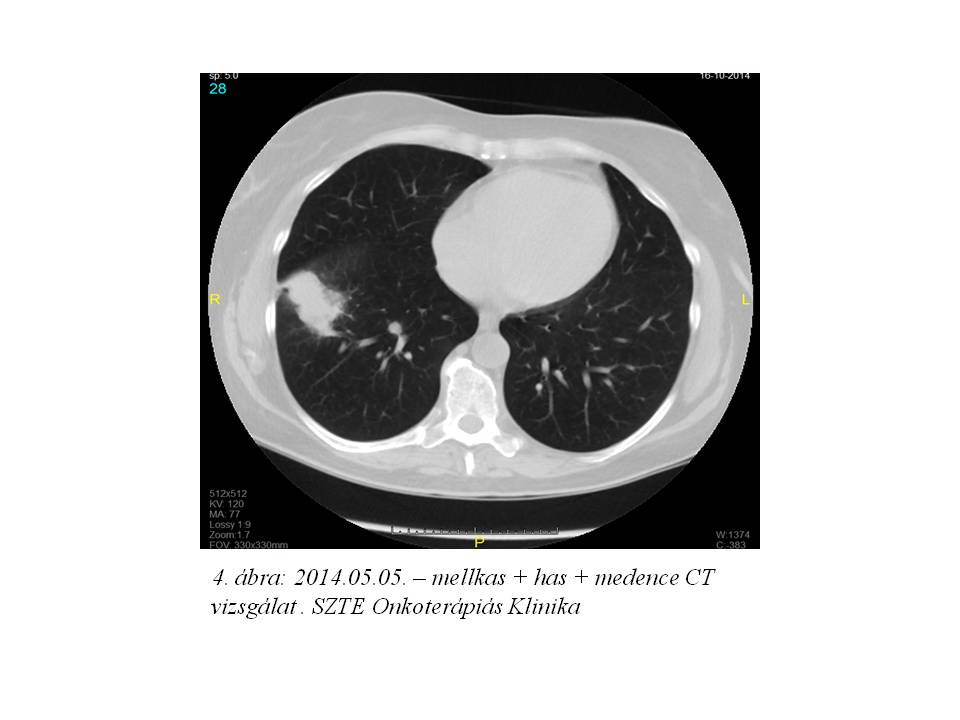

2014. márciusban a beteg rendellenes hüvelyi vérzés miatt jelentkezett nőgyógyászati kontrollon. Fizikális vizsgálattal egyértelműen recidíva nem igazolódott. Has + kismedencei CT vizsgálat történt, mely multiplex hepaticus metastasisokat, valamint jobb oldali pyelectasia mellett a hólyag és a rectum közötti régióban kismedencei recidíva radiológiai képét, és a jobb tüdőbázison is bizonytalan gócot írt le. (1. ábra, 2. ábra, 3. ábra, 4. ábra).